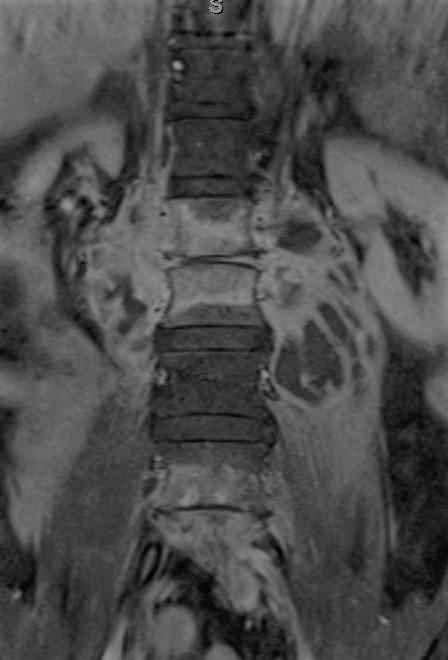

Case Presentation: A 62-year-old man presented with six months of progressive lower back pain. He noticed weight loss, sweats, and subjective fevers, but denied neurological symptoms or a other complaints. Patient lives in Texas, but travels to Mexico during winter. He denied tobacco abuse, intravenous drug use, incarceration or animal exposure. He reported eating unpasteurized cheese one year ago in Cuba and Mexico. Physical examination was positive for mild lumbar vertebral tenderness. Labs included an erythrocyte sedimentation rate of 64 mm/h and C-reactive protein of 4.4 mg /dL. White blood count was normal. Magnetic Resonance Imaging (MRI) of the lumbar spine showed infective lumbar spondylitis at L1-L2 and L4-L5 with extensive bilateral psoas abscesses. Blood and abscess aspirate cultures were obtained, and the patient was started on anti-tuberculosis medications given the classic MRI features of for tuberculosis. Abscess aspirate grew Brucella melitensis and anti-tuberculosis medications were changed to gentamycin and doxycycline